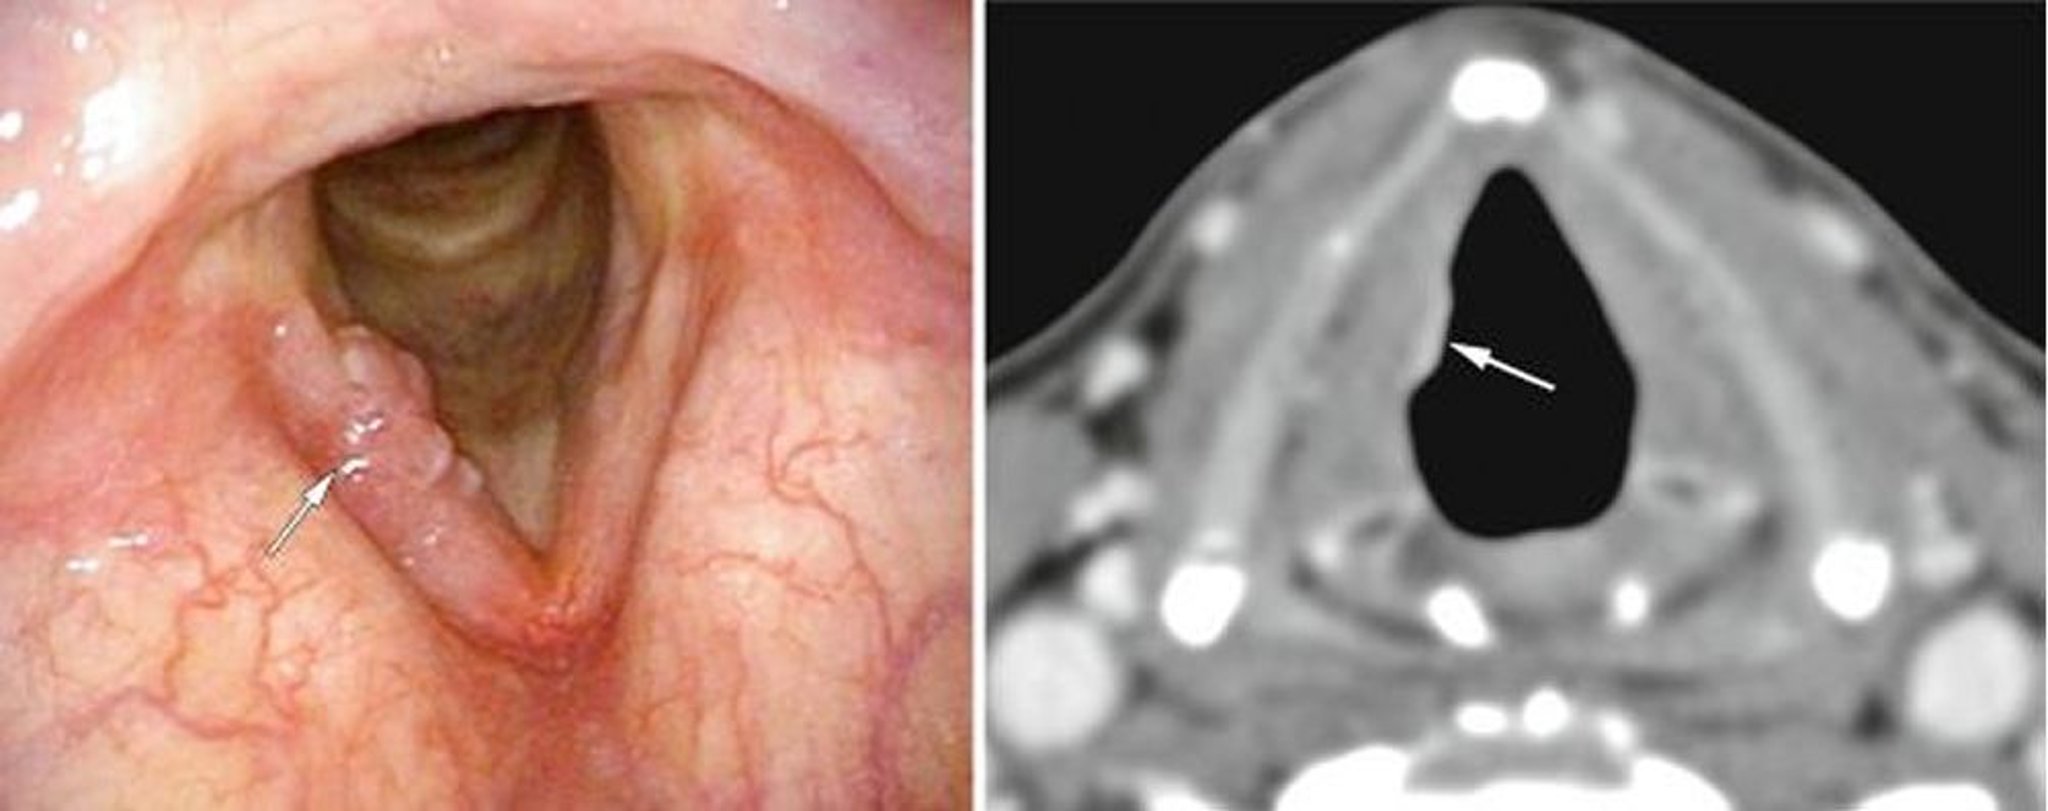

Ung thư thanh quản giai đoạn sớm

Bệnh nhân này bị ung thư thanh quản thanh môn giai đoạn sớm, có thể thấy các cục lồi trên một dây thanh âm trên ảnh nội soi (ảnh trái, mũi tên màu trắng), và có thể thấy tích tụ mô mềm bất thường trên CT (ảnh phải, mũi tên màu trắng).